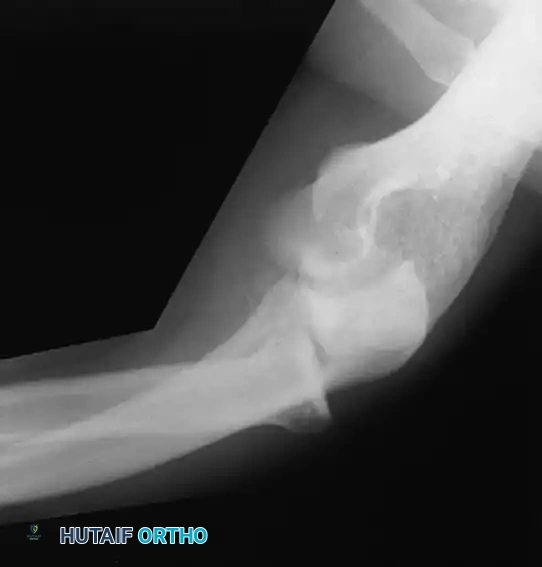

Diagnostic Imaging

Diagnostic radiographs must include an anteroposterior (AP) view, a true lateral view, and two 45-degree oblique views to evaluate the radiocapitellar and ulnohumeral joints. In patients with chronic medial symptoms, a Jones view (acute flexion AP) is indicated to identify posteromedial olecranon osteophytes.

A gravity stress radiograph can be obtained with the patient supine, shoulder abducted 90 degrees, and externally rotated. A lateral radiograph demonstrates medial opening under gravity stress.